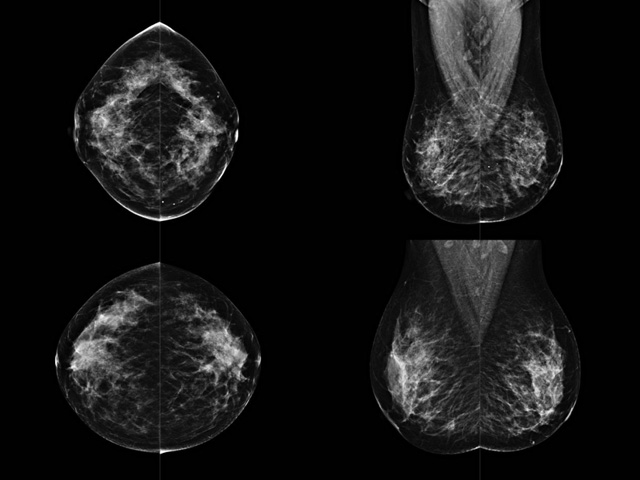

乳房检查时候要注意一些细节,需要更深入的了解这样才能使检查更准确。乳腺DR是乳腺癌的筛查诊断工具设备。是乳房方面检查的重要影像方法。它可以临床检查出早期的乳腺癌。可以判断良性恶性。因为它可以检查出早期的病变。对良性恶性检查的准确率达到90%以上。发病高峰年龄为45岁到54岁。50岁检查出来乳腺癌病患,可以让死亡率下降3成。所以30-40岁女性每年做一次乳腺DR检查。40岁以上就一年两次。如果家族史有乳腺癌的30岁以下也需要做检查。清晰显示乳腺各层组织严重的乳腺增生,乳腺炎,乳腺外伤也建议1年检查一次。极大提高了早期乳腺癌的敏感度和诊断率。

大角度、高质量的乳腺检查,可以让女性带来身体健康安全。为医生提供了高清影像数据。乳腺检查时候各个部位影像显示出来。白色乳腺导管跟纤维结缔组织。模糊的是脂肪。病变一般是不透明的白色。有需要放大来检查。乳腺DR没有重叠伪影。辐射剂量更少。因为乳腺癌发病每年都有所提高,对女性都造成了严重的身体健康危害。早做检查早治疗是不可忽视的举措??梢源蟠蟮慕档?/span>死亡率。保证身体健康。一般检查避开经期,来完7天左右是最佳的检查时间。绝经的女性就没有要求。孕妇不参加乳腺DR检查, 6个月内准备妊娠的妇女也不宜行此检查。